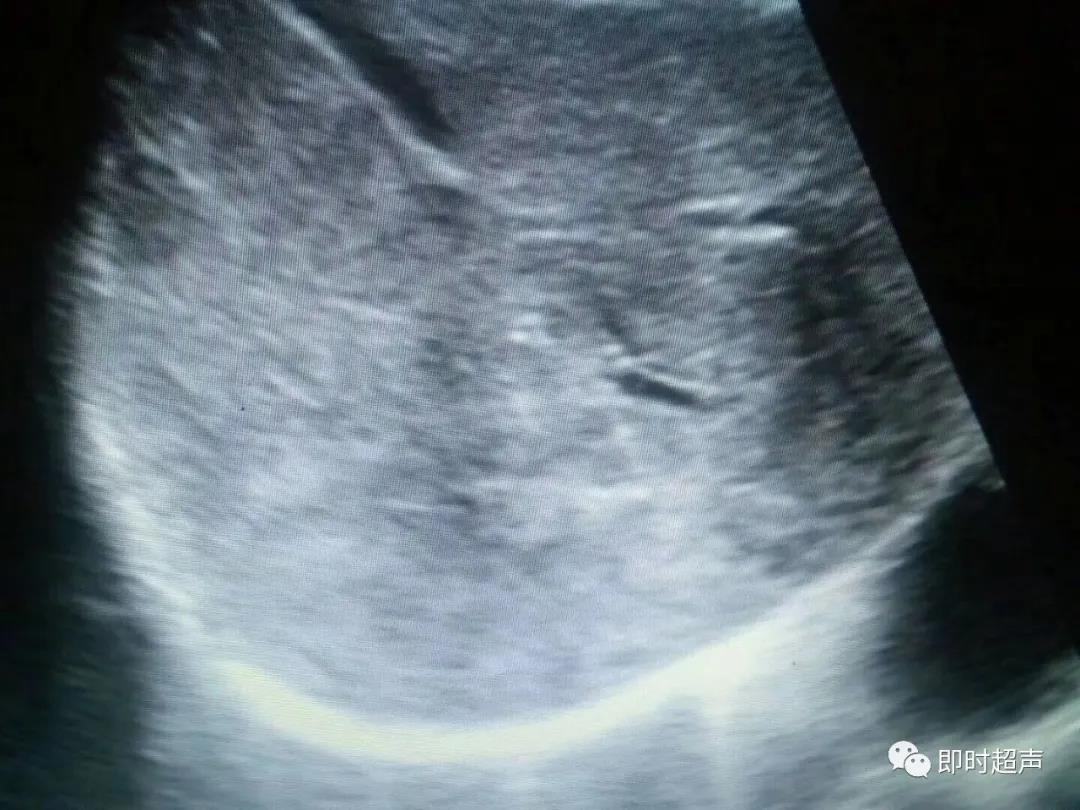

肝血吸虫病的二维超声

显示肝内回声增强增粗呈网状,地图肝

3.也可呈现高回声纤维条索或网格样结构,将肝实质分隔成不同大小的区域,类似地图,故称地图肝。

超声显示:肝实质呈弥漫的网格状回声增强,即飘雪征,为血吸虫肝所特有的典型声像图改变。结合临床血尿阳性检查结果故诊断肝血吸虫病。